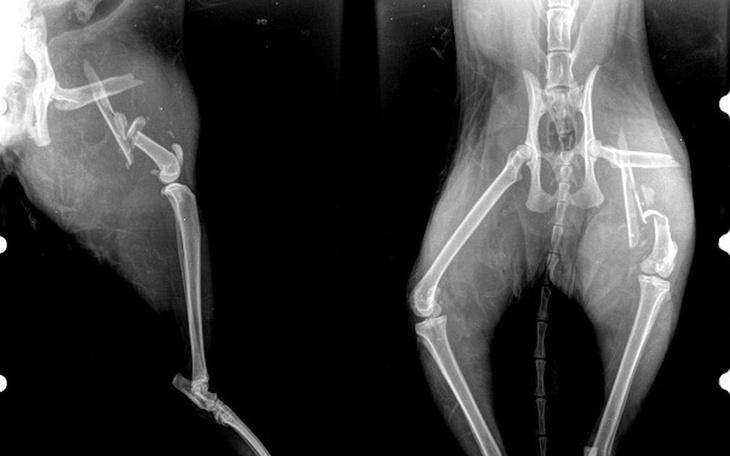

EDYCJA_7____ Dzisiaj byłyśmy w PRO-VET na zdjęcie szwów i zmianę opatrunku. Pan weterynarz mówi że jak na razie wszystko wygląda dobrze, kolejna wizyta 28.08.2017, wtedy zrobimy zdjęcie RTG i zobaczymy jak to wygląda w środku. Miejmy nadzieję że nowy opatrunek w 4-listna koniczynka przyniesie szczęście :-D ____PROSZĘ UDOSTĘPNIAJCIE ZBIÓRKĘ____każda złotówka się przyda :-*